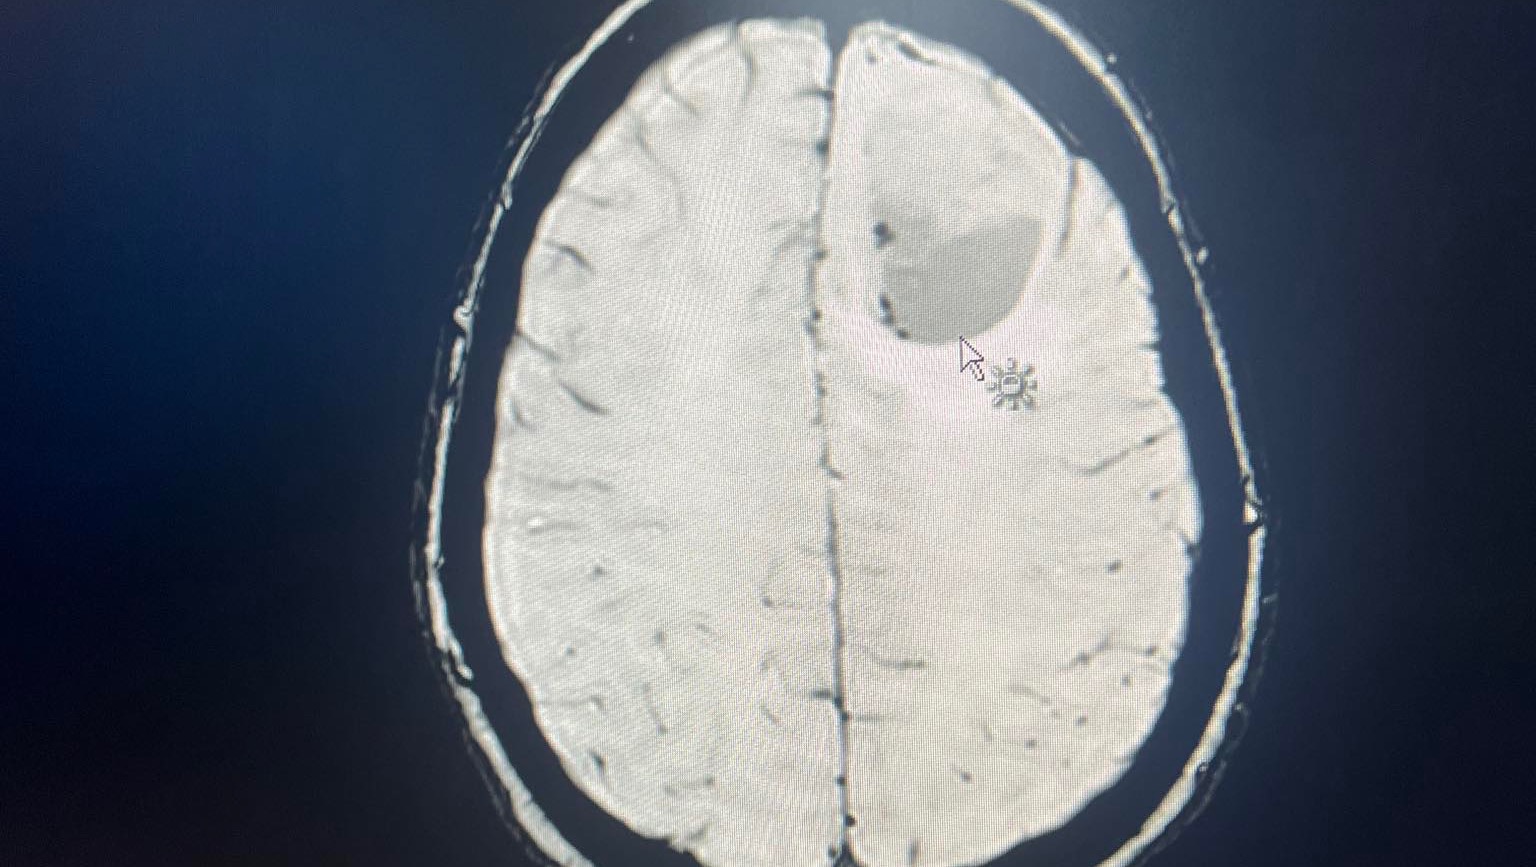

Update from Hannah- yesterday Becca had her results and has been diagnosed with stage 4, terminal astrocytoma brain cancer. Extremely shit and not what we wanted to hear, but we are going to give everything we can now!

After going to hospital with headaches, she was given devastating news later that same night: a 4cm brain tumour. Within days, Becca underwent urgent surgery at Leeds General Infirmary to remove the tumour.